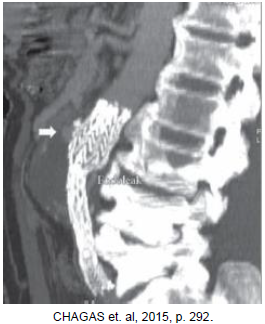

Qual o tipo de endoleak se observa na imagem abaixo?